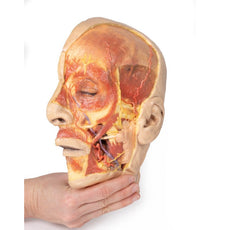

The head and neck of the specimen provides views of both superficial and deep structures in the region. The calotte has been removed ~2cm superior to the orbits to expose the brain in relation to the endocranial cavity. The transverse section through the cerebrum demonstrates the relation of the grey matter cortex to the white matter medulla, as well as the lateral ventricles with a small amount of choroid plexus visible in the base of both spaces. The skin and superficial fascia on the right side has been retained and false-coloured to display the angiosomes of the face and posterior neck. On the left side, the superficial tissues have been dissected to expose the muscles of facial expression, muscles of mastication, and deeper structures of the infratemporal fossa including the lingual nerve, terminal branches of the external carotid artery into the superficial temporal and maxillary arteries.

The carotid sheath has been opened on both sides of the neck, and the internal jugular veins and sternocleidomastoid muscles largely removed, to expose the pathway of the common carotid arteries, internal and external carotid arteries, and the vagus nerves. On the right side, the great auricular nerve ascends towards the face, while the hypoglossal nerve can be seen adjacent to the exposed stylohyoid ligament and supra- and infrahyoid muscles. A large thyroid gland is present bilaterally inferior to the thyroid cartilage, with a well-preserved superior thyroid artery and inferior thyroid vein on the right side and across the midline.

The head and neck of the specimen provides views of both superficial and deep structures in the region. The calotte has been removed ~2cm superior to the orbits to expose the brain in relation to the endocranial cavity. The transverse section through the cerebrum demonstrates the relation of the grey matter cortex to the white matter medulla, as well as the lateral ventricles with a small amount of choroid plexus visible in the base of both spaces. The skin and superficial fascia on the right side has been retained and false-coloured to display the angiosomes of the face and posterior neck. On the left side, the superficial tissues have been dissected to expose the muscles of facial expression, muscles of mastication, and deeper structures of the infratemporal fossa including the lingual nerve, terminal branches of the external carotid artery into the superficial temporal and maxillary arteries.

The carotid sheath has been opened on both sides of the neck, and the internal jugular veins and sternocleidomastoid muscles largely removed, to expose the pathway of the common carotid arteries, internal and external carotid arteries, and the vagus nerves. On the right side, the great auricular nerve ascends towards the face, while the hypoglossal nerve can be seen adjacent to the exposed stylohyoid ligament and supra- and infrahyoid muscles. A large thyroid gland is present bilaterally inferior to the thyroid cartilage, with a well-preserved superior thyroid artery and inferior thyroid vein on the right side and across the midline.